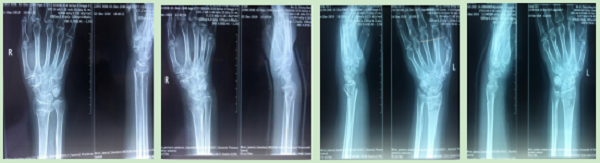

手法整复桡骨远端骨折、肱骨骨折、踝关节骨折、掌骨骨折、指骨骨折、跖骨骨折及肩关节脱位、桡骨小头半脱位等各类骨折脱位十余例,行小夹板固定及石膏托外固定十余例。